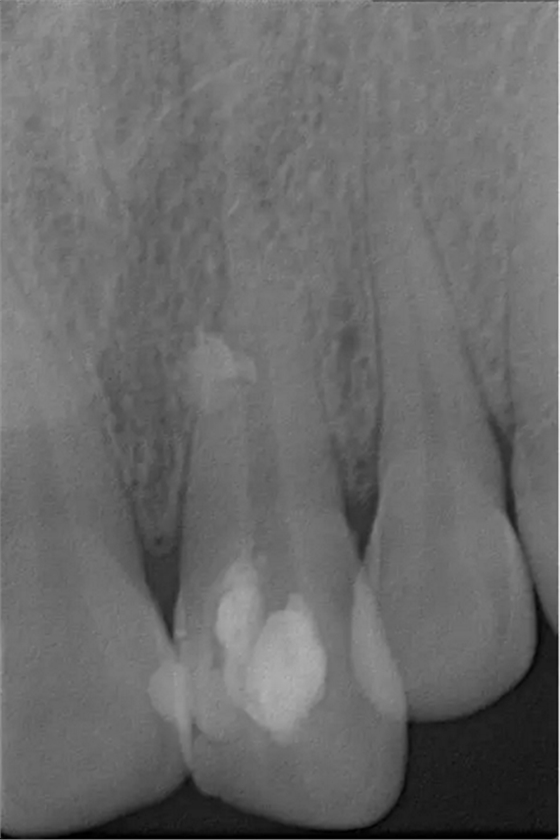

患者女,年齡35左右,牙位21,根管治療曾經(jīng)歷過(guò)外院四到五次等不同地方的處理,還是不能咬硬物,會(huì)有酸、軟、痛的情況出現(xiàn),偶有自發(fā)疼痛,2016年9月初,轉(zhuǎn)診至我處治療21。術(shù)前拍片發(fā)現(xiàn)根中部存在側(cè)穿,橡皮障下常規(guī)再治療,隨后減輕了軟和痛的情況。因?yàn)閭?cè)穿,牙周膜受到牙膠尖等異物的持續(xù)刺激,酸軟的情況還是持續(xù)存在,所以決定行根尖外科手術(shù),采用MTA修補(bǔ)穿孔點(diǎn)。術(shù)后觀察半年左右,所有癥狀消除后,隨后熱牙膠充填。

術(shù)前診斷片